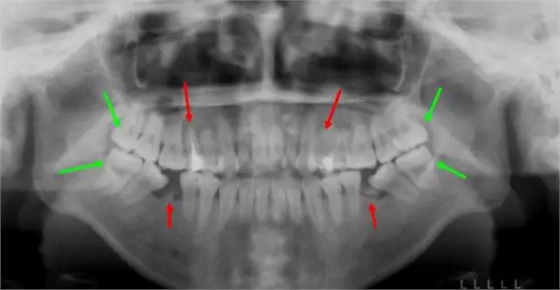

當(dāng)牙齒有嚴(yán)重的齲壞、發(fā)育不良、畸形及錯位等情況時,也會有除4/5號牙以外的非常規(guī)性拔牙,Dr.貝用個例子來說明!

普瑞美口腔——歐陽莉醫(yī)生案例:

這個妹子正畸前,前牙不能咬合,牙凸又嘴凸而且還有殘余的牙根,牙列開始傾斜。綜合考慮后,醫(yī)生拔除了箭頭所示8顆牙,沒有采取常規(guī)拔牙,因為需要盡量拔除不能保留的病牙。

矯正結(jié)束后,姑娘收獲了整齊的牙齒和完美的微笑~